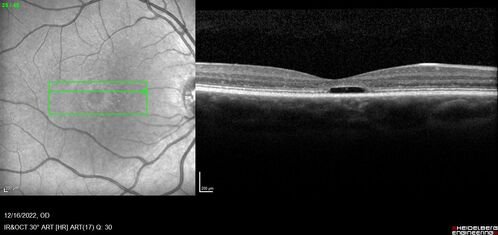

Stargardt Disease - Very Mild - 24 year old

This patient has 3 different ABCA4 mutations. His mother and sister have stargardts and his father has RP. His sisters images are also on Retinagallery.com